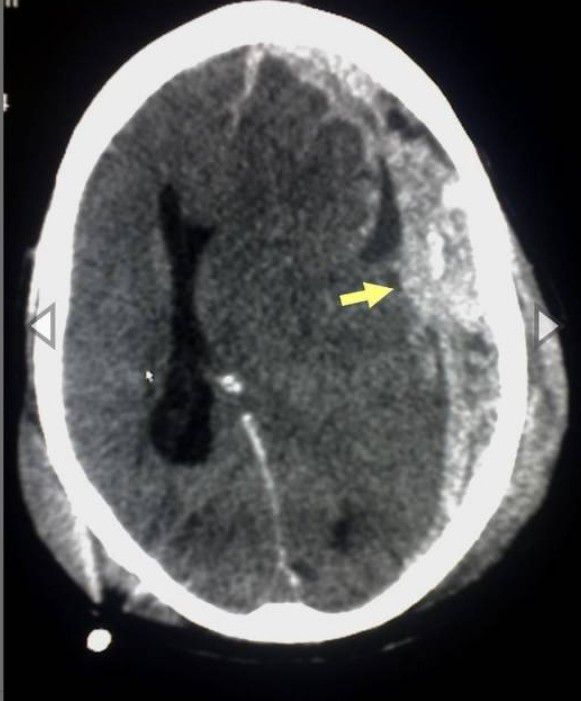

Neurosurgery

Neurosurgeon